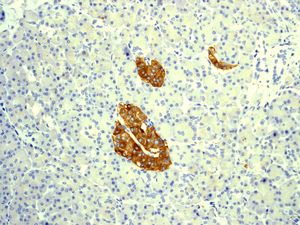

Immunohistochemical analysis of paraffin-embedded human pancreas tissue using anti-Synaptophysin RabMAb (cat. APR13618G). |